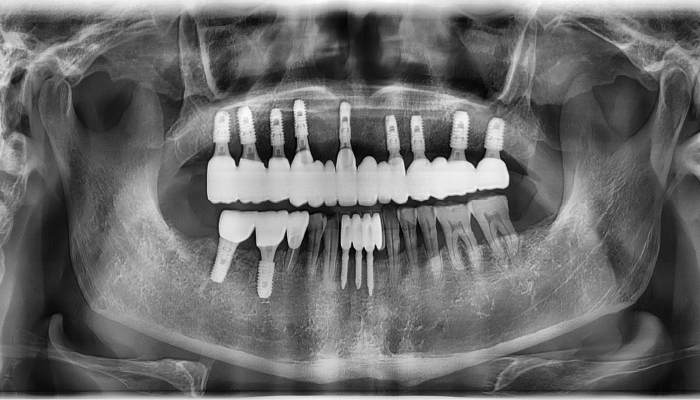

뼈이식 임플란트 전후 사례

식립 후

식립후